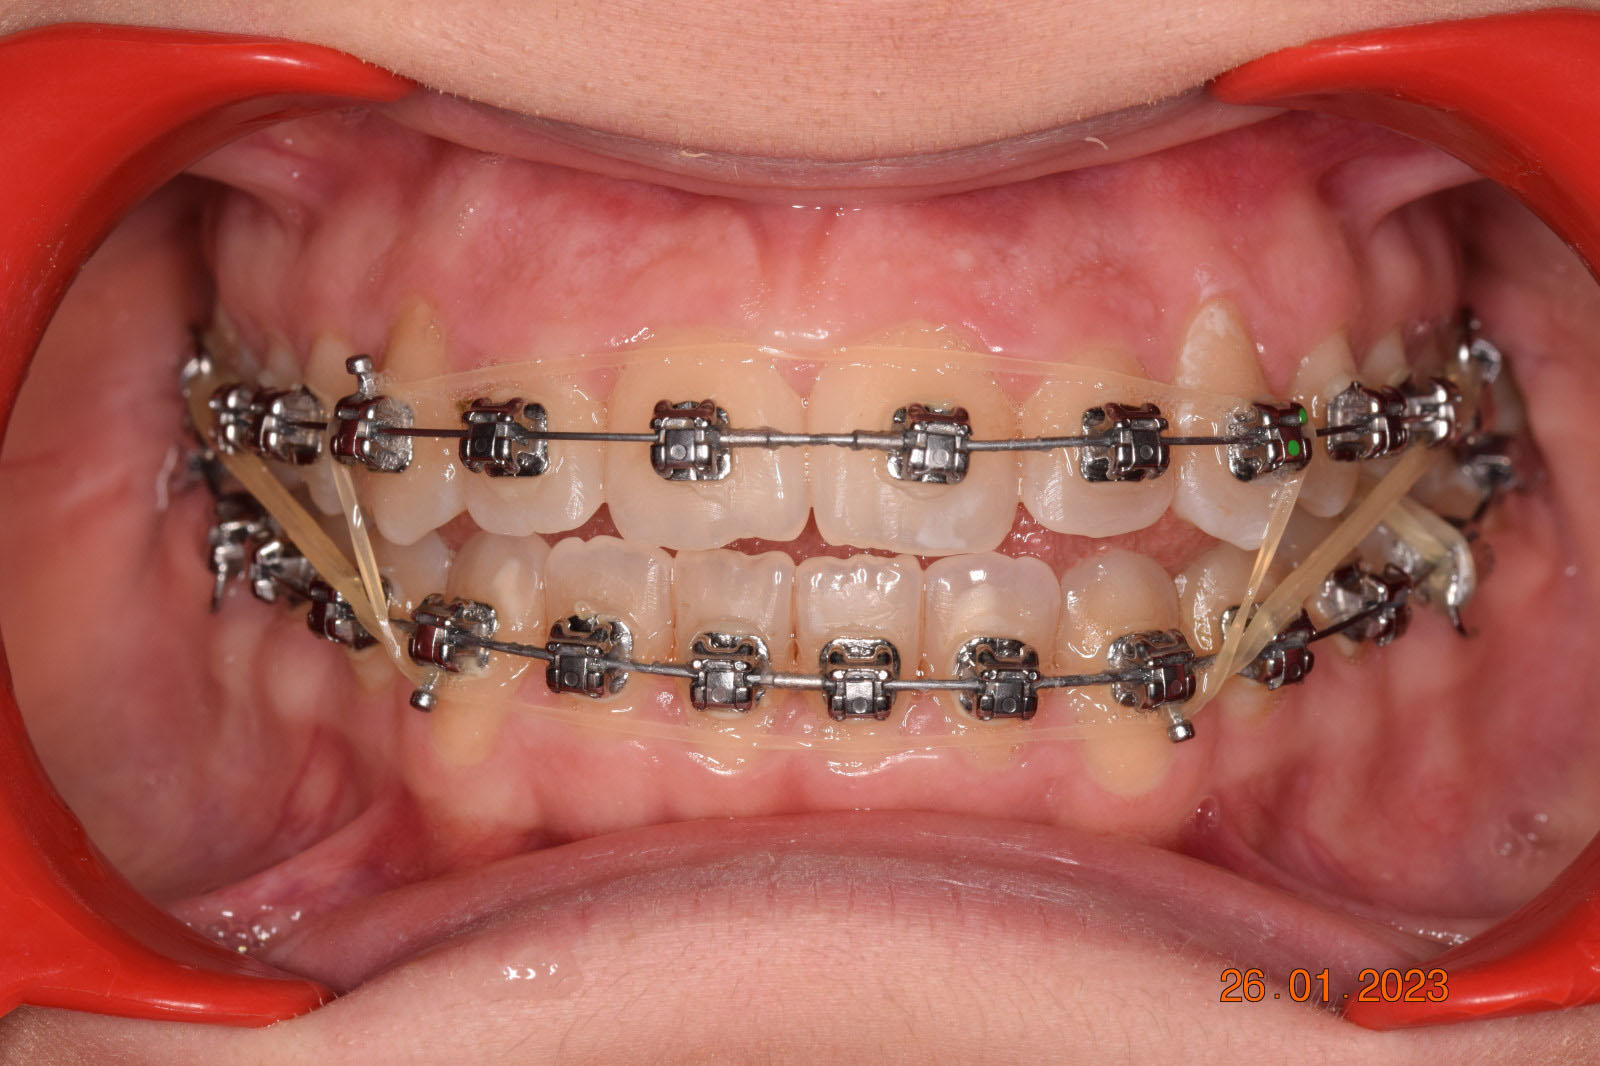

The treatment began in 2017. Given the patient’s preference for less visible brackets, Damon Clear brackets were selected. High torque upper cuspids and low torque upper incisors were chosen to offer the best torque control for upper arch development. For the lower arch, there were no alternative bracket configurations available. Bite turbos were applied to the upper second molars.

The results were unsatisfactory and the patient began losing interest in the treatment. Dr. Coca and the patient agreed to extend the treatment for six more months and then stop, regardless of the outcome.

This case posed challenges in all three spatial dimensions, compounded by significant crowding. The patient was highly compliant and maintained excellent oral hygiene throughout the 5.5 years of treatment, which required more than 30 clinical appointments.